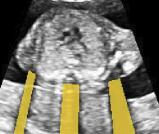

Sound-opaque occluders, including bones and calcified tissues, block the propagation of sound waves by strongly absorbing or reflecting sound waves during scanning. The regions behind these sound-opaque occluders return little to no reflections to the US transducer. Thus these areas have low intensity but very high acoustic impedance gradients at their boundaries (e.g. Fig. 1(a) left column). Reducing acoustic shadows and correct interpretation of images containing shadows rely heavily on sonographer experience. Experienced sonographers avoid shadows by moving the probe to a more preferable viewing direction during scanning or, if no shadow-free viewing direction can be found, a mental map is compounded with iterative acquisitions from different orientations.

![]() |

|